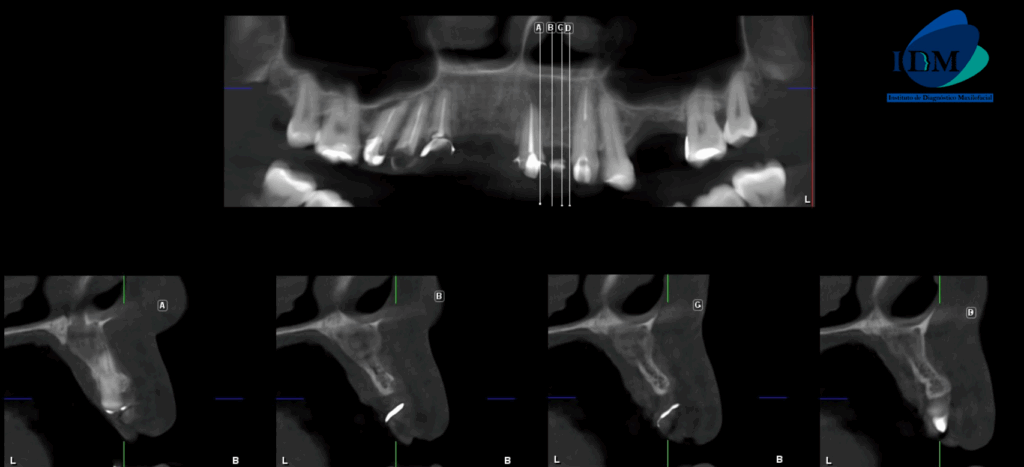

A la evaluación de la tomografía volumétrica (CBCT) en los cortes axiales (Figura 2) y transaxiales (Figura 3), se aprecia imagen mixta localizada a nivel apical de pieza 21, de limites definidos, que se extiende en sentido cefálico caudal desde piso de fosa nasal izquierda hasta apical de pieza 21, en sentido mesio distal desde cortical de conducto nasopalatino hasta nivel de zona de pieza 22, ocasionando adelgazamiento y expansión de tabla ósea vestibular y palatina, adelgazamiento del piso de fosa nasal izquierda, borramiento parcial de cortical de conducto nasopalatino.

CORTES TRANSAXIALES